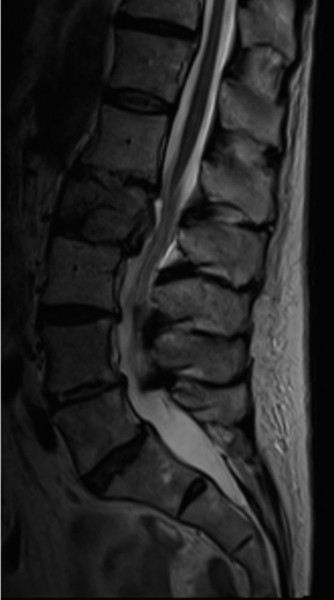

fractures of the anterior or posterior elements. The hallmark feature is a translation deformity that can be noted by misalignment of the vertebral bodies in the coronal and/or sagittal planes. A lumbar spine MRI is obtained, images from which are shown inFigures 1–34 and 1–35. Based on the information presented, the type of neurological injury is best characterized as which of the following? 1. Cauda equina injury

Figure 1–34

Figure 1–35

The correct answer is (A). The MRI demonstrates the L2 fracture with canal compromise. In this patient, the conus medullaris of the spinal cord terminates at the T12–L1 level. The fracture is at the L2 level. Thus, the neurological injury is at the level of the cauda equina, distal to the conus medullaris and spinal cord. The patient’s neurological examination is consistent with this type of injury with the presence of lower extremity weakness, intact rectal tone, and perineal numbness, though this can vary.